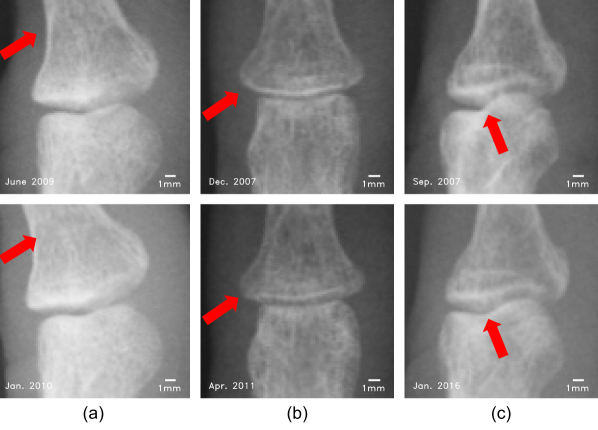

Radiology plays a crucial role in diagnosis and monitoring of RA. Clinical radiologist/rheumatologist can assess the radiographic progression of RA by using the Sharp/van der Heijde scoring method (SvdH). This method relies on scoring of the radiographies by subjectively assessing JSN and bone erosion of 383838 hand or foot joints [5]. JSN progression is one of the most important indicators in RA treatment, as it can directly impact medication. Limited by the current spatial resolution of radiographic imaging, JSN progression over a period of one year can be less than one pixel, as show in Fig. 1. This means that the pixel-level accuracy algorithm requires more time to wait for the change of joint space. Nevertheless, this can lead to insensitive monitoring of JSN progression, and this may hinder the radiologist/rheumatologist from making a proper diagnosis in the ”window of opportunity” [6, 7, 8].

Refer to caption

Figure 2: Schematic overview of joint position detection. The approximate areas of fingers are obtained according to each pair of local maxima (red points) and local minima (green points) in binary image. Then, the finger midlines (blue lines) are calculated by fitting to each area. Finally, an AdaBoost based joint classifier is used to detect the joint positions (red windows).

Figure 12: Joints with mismatched registration. (a) Inconsistent joint angle. (b) Bended finger. (c) Inconsistent projection angle.

According to our experiments, changes in bone contours can affects the accuracy of JSN quantification. Here, we showcase (see Fig. 12) majority of mismatch bone contour cases. The most frequent reason is the inconsistent angle between the upper and lower bones of joint, as show in Fig. 12 (a). This mainly occurs on IP and MCP joints. PIPOC has high accuracy for translation detection, but weak resistance to rotation. Another important reason of mismatched registration is the bending of the fingers, which appears on DIP and PIP joints, for an example see Fig. 12 (b). Finger bending can result in the changes of the far margin appearance of upper bone. Besides, inconsistent projection angle also can be the reason, see Fig. 12 (c). Most of the time it happens only on the IP joint, which is caused by inconsistent joint position or thumb roll. The individuated finger movements differ greatly as studied in [50]. Movements of the thumb, index finger, and little finger typically were more highly individuated than were movements of the middle or ring fingers. The angular motion tended to be greatest at the PIP joint of each digit [50]. It is worth noting that, the flexibility of joint and standard deviation express high positive correlation (refer Table 6).